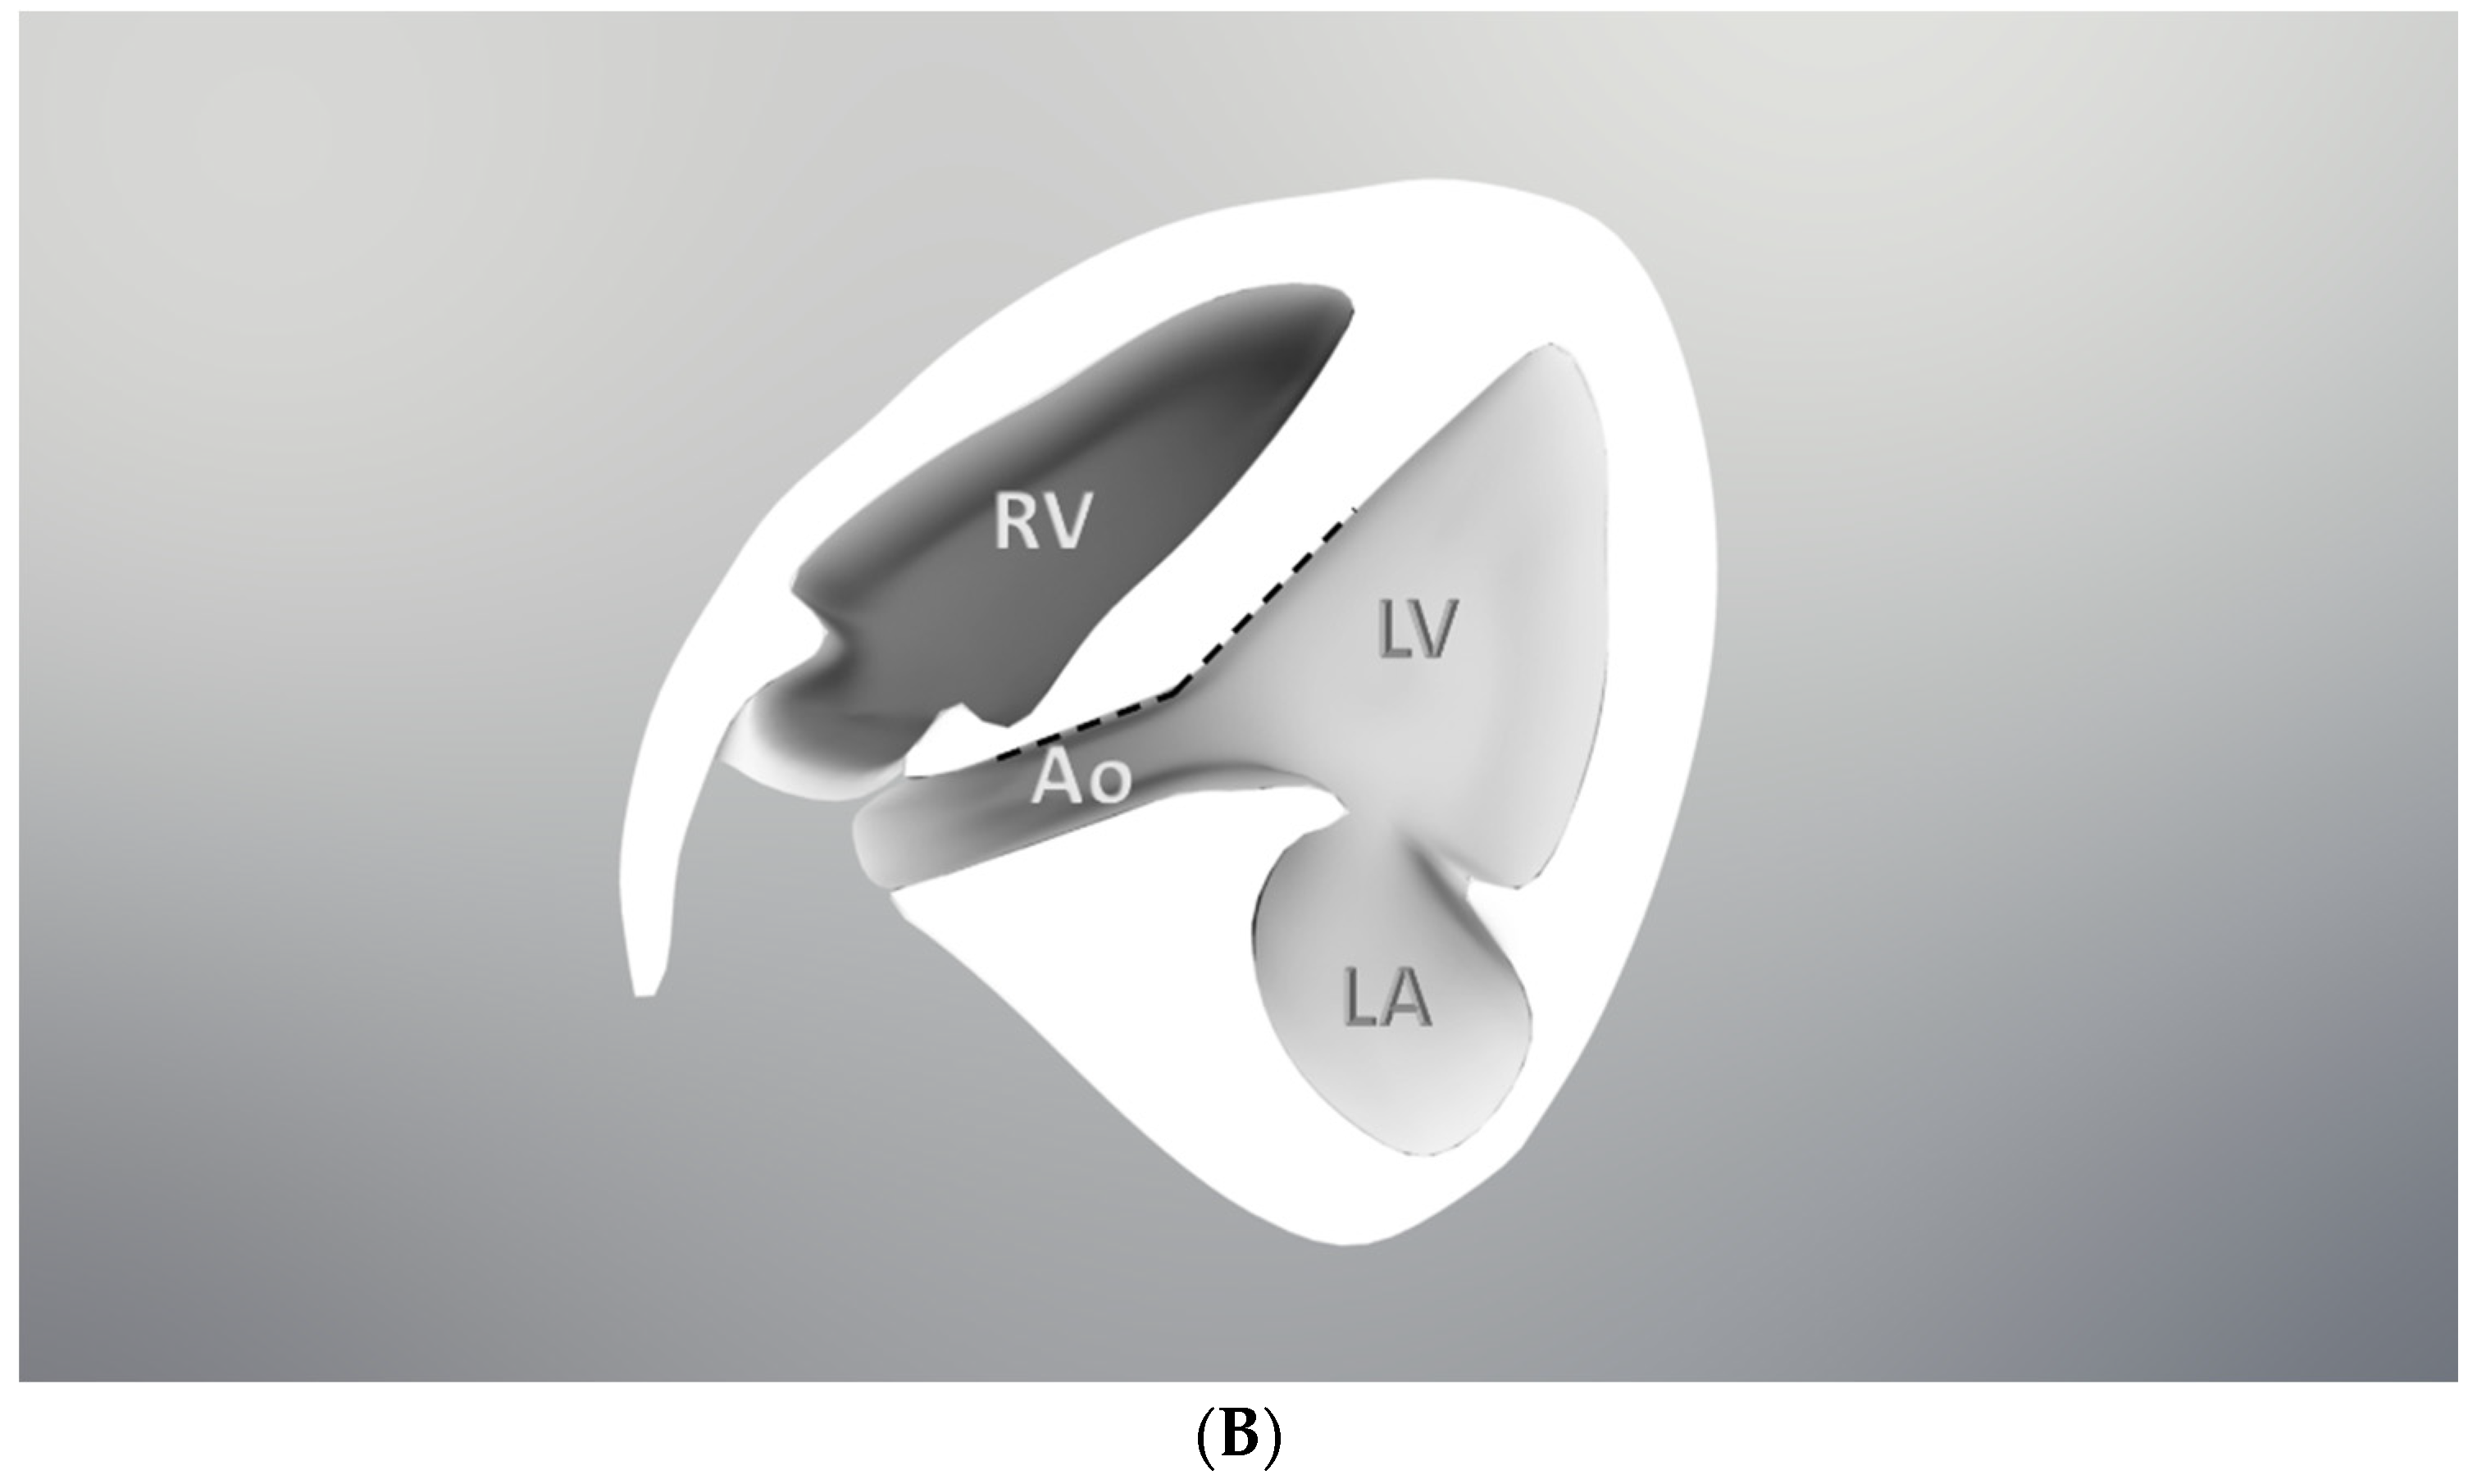

2. Methods

3. Results